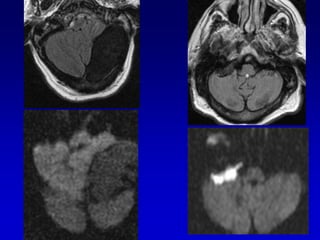

3 QUISTE EPIDERMOIDE

Epidermoide

DWIFLAIR